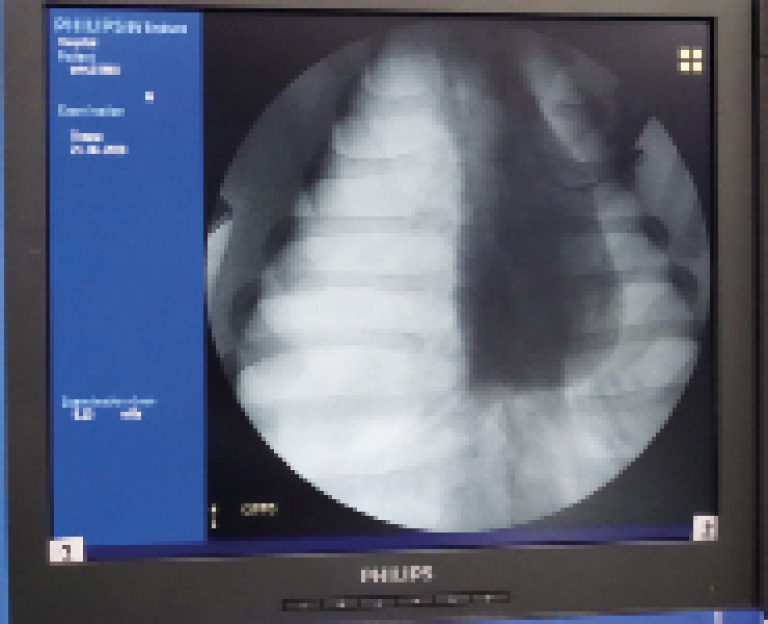

Эксперимент 1. Моделирование и устранение напряженного пневмоторакса на крупном лабораторном животном. В IV межреберье по передней подмышечной линии устанавливался катетер, который далее подключался к инсуфлятору эндовидеохирургической стойки для создания карбокситоракса (рис. 2). Подача CO2 осуществлялась со скоростью 3 л/мин до получения значения карбокситоракса, равного 15 мм рт. ст., напряженный пневмоторакс подтверждался данными рентгенограммы груди (рис. 3).

Рис. 3. Рентгенограмма груди. Напряженный пневмоторакс, средостение смещено влево